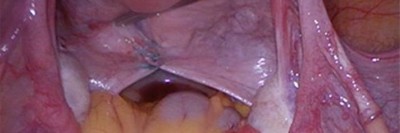

Eine 26-jährige Drittgravida stellt sich mit starken linksseitigen Unterbauchschmerzen vor. Ein Jahr zuvor hatte sie ein Amnioninfektionssyndrom mit Spätabort erlitten. Es folgten eine Nachkürettage und eine ausgeprägte postoperative Endomyometritis mit schwerem septischem Verlauf. Bei der diagnostischen Laparoskopie und Hysteroskopie zur weiteren Abklärung zeigte sich ein eindeutig pathologischer Befund.

Bildnachweise